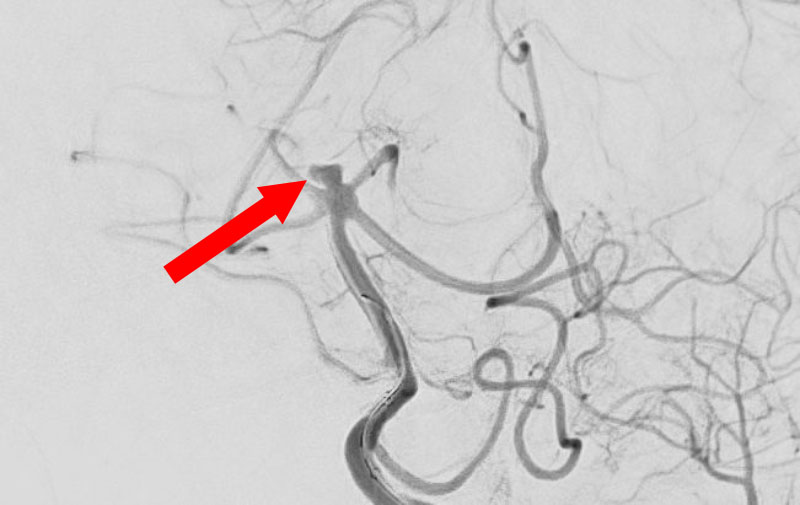

くも膜下出血

破裂性内頚動脈解離

40代

救急外来

No.1594 手術前

No.1594 手術中

No.1594 手術後